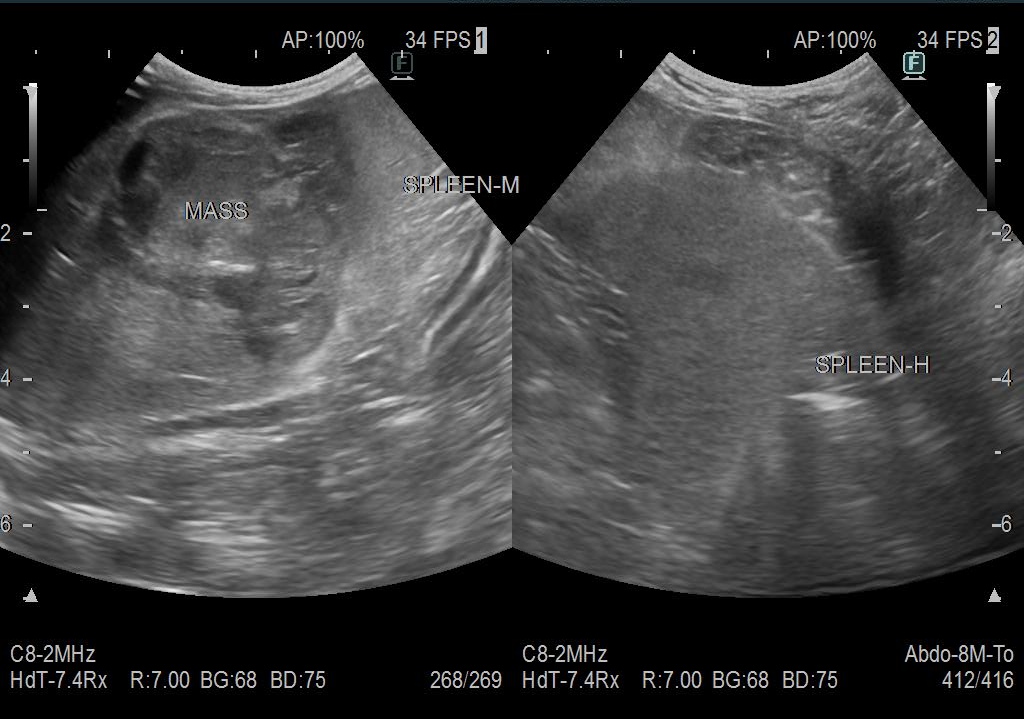

レントゲン検査、超音波検査にて脾臓に大きなしこりが見つかりました。

(今回の胃腸障害・発熱は、脾臓のしこりが小破裂をしたところにお腹の中の脂肪が癒着したため炎症が起きて腹膜炎に繋がったためと推測されました)